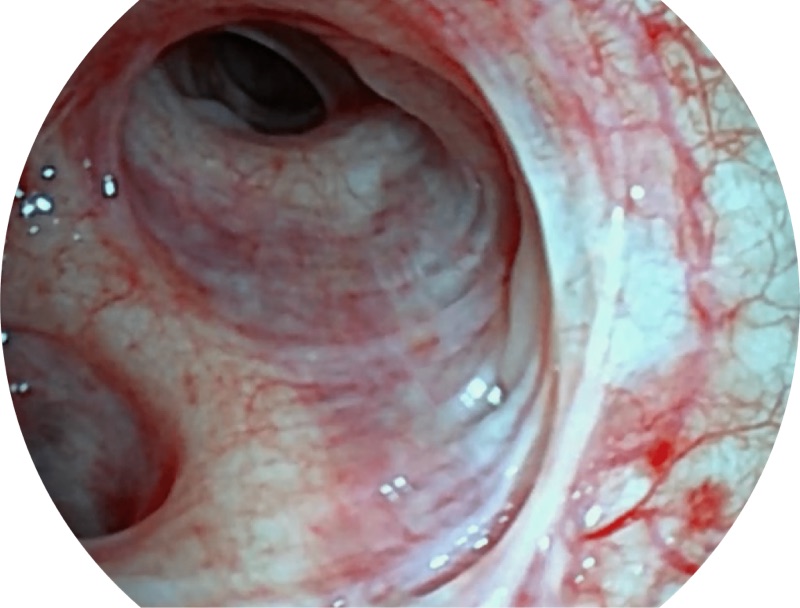

EB-5H20具有4.9mm外径及2.0mm钳道提升对外围支气管检查能力

帮助医生更加清晰地观察气管表面病灶